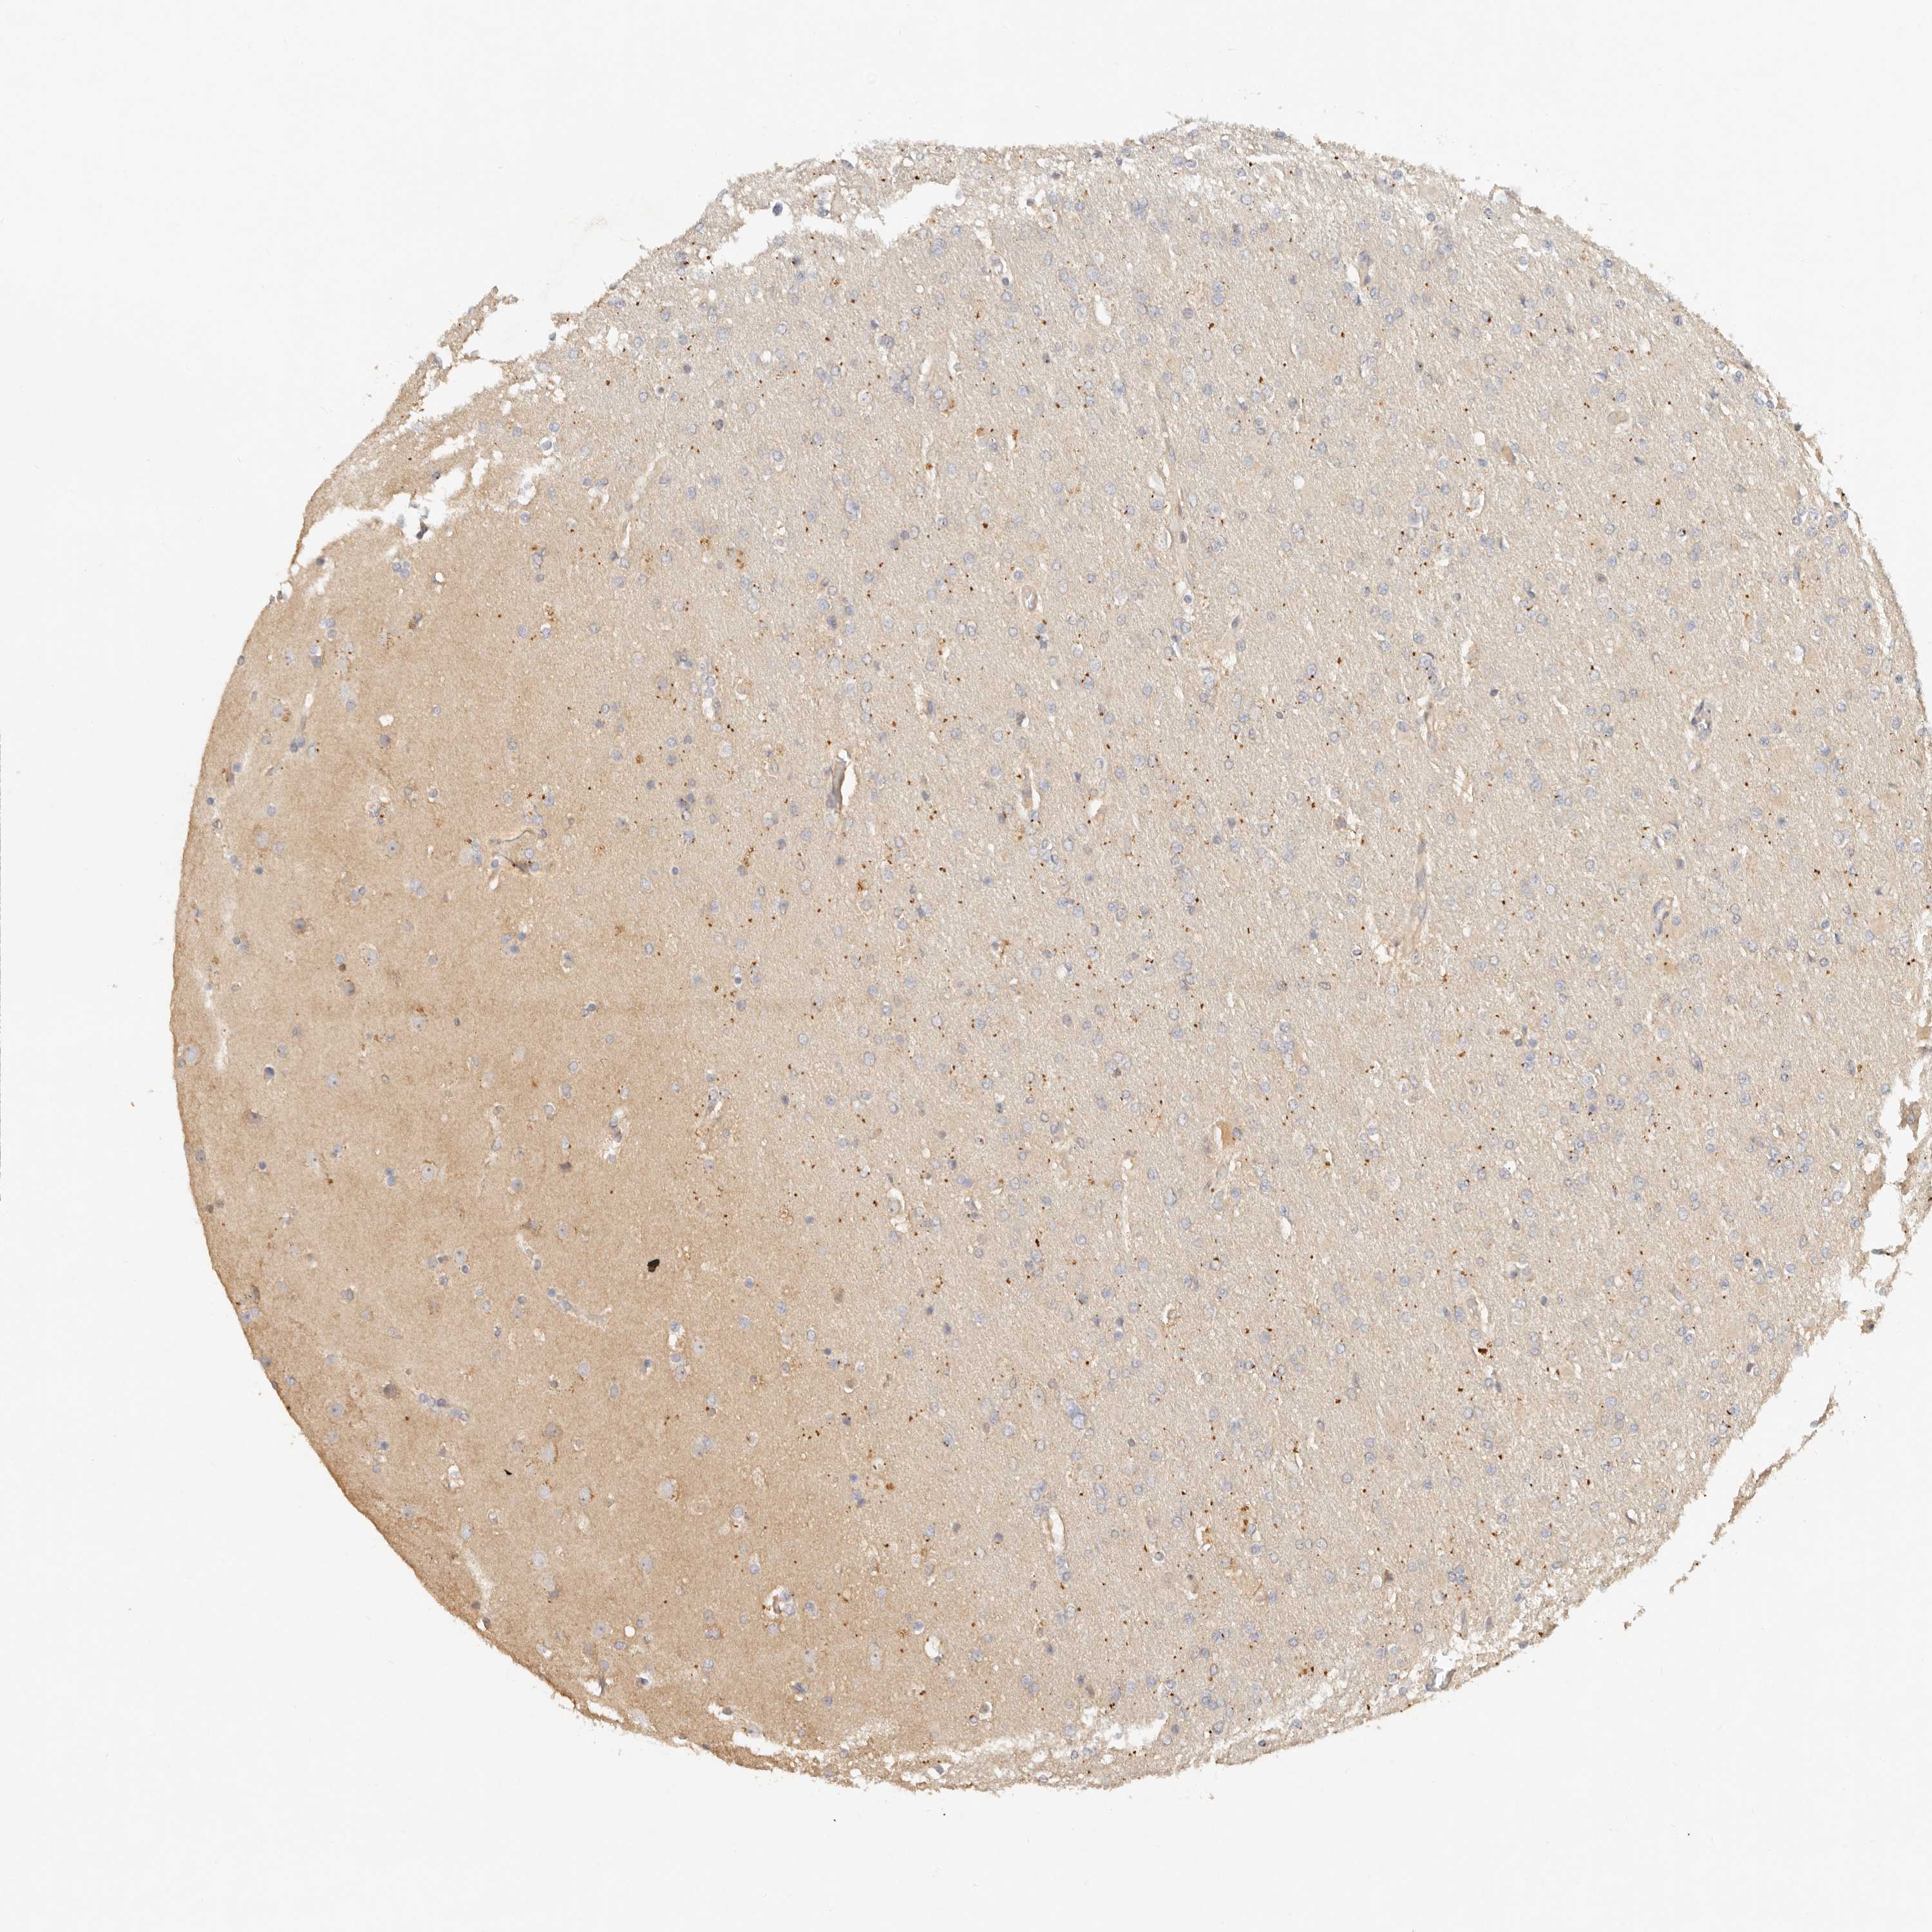

GLIOMA - Protein expressioni

A mouse-over function shows sample information and annotation data. Click on an image to view it in a full screen mode. Samples can be filtered based on level of antibody staining by selecting one or several of the following categories: high, medium, low and not detected. The assay and annotation is described here.

Note that samples used for immunohistochemistry by the Human Protein Atlas do not correspond to samples in the TCGA dataset.

Antibody stainingi

Antibody staining in the annotated cell types in the current human tissue is reported as not detected, low, medium, or high, based on conventional immunohistochemistry profiling in selected tissues. This score is based on the combination of the staining intensity and fraction of stained cells.

Each image is clickable and will lead to virtual microscopy that enables deeper exploration of all samples and also displays staining intensity scores, fraction scores and subcellular localization as well as patient and tissue information for each sample.

Antibody HPA027467

Staining

High

Medium

Low

Not detected

Intensity

Strong

Moderate

Weak

Negative

Quantity

>75%

75%-25%

<25%

None

Location

Nuclear

Cytoplasmic/membranous

Cytoplasmic/membranous,nuclear

Glioma, malignant, High grade

Glioma, malignant, Low grade

Glioblastoma, NOS